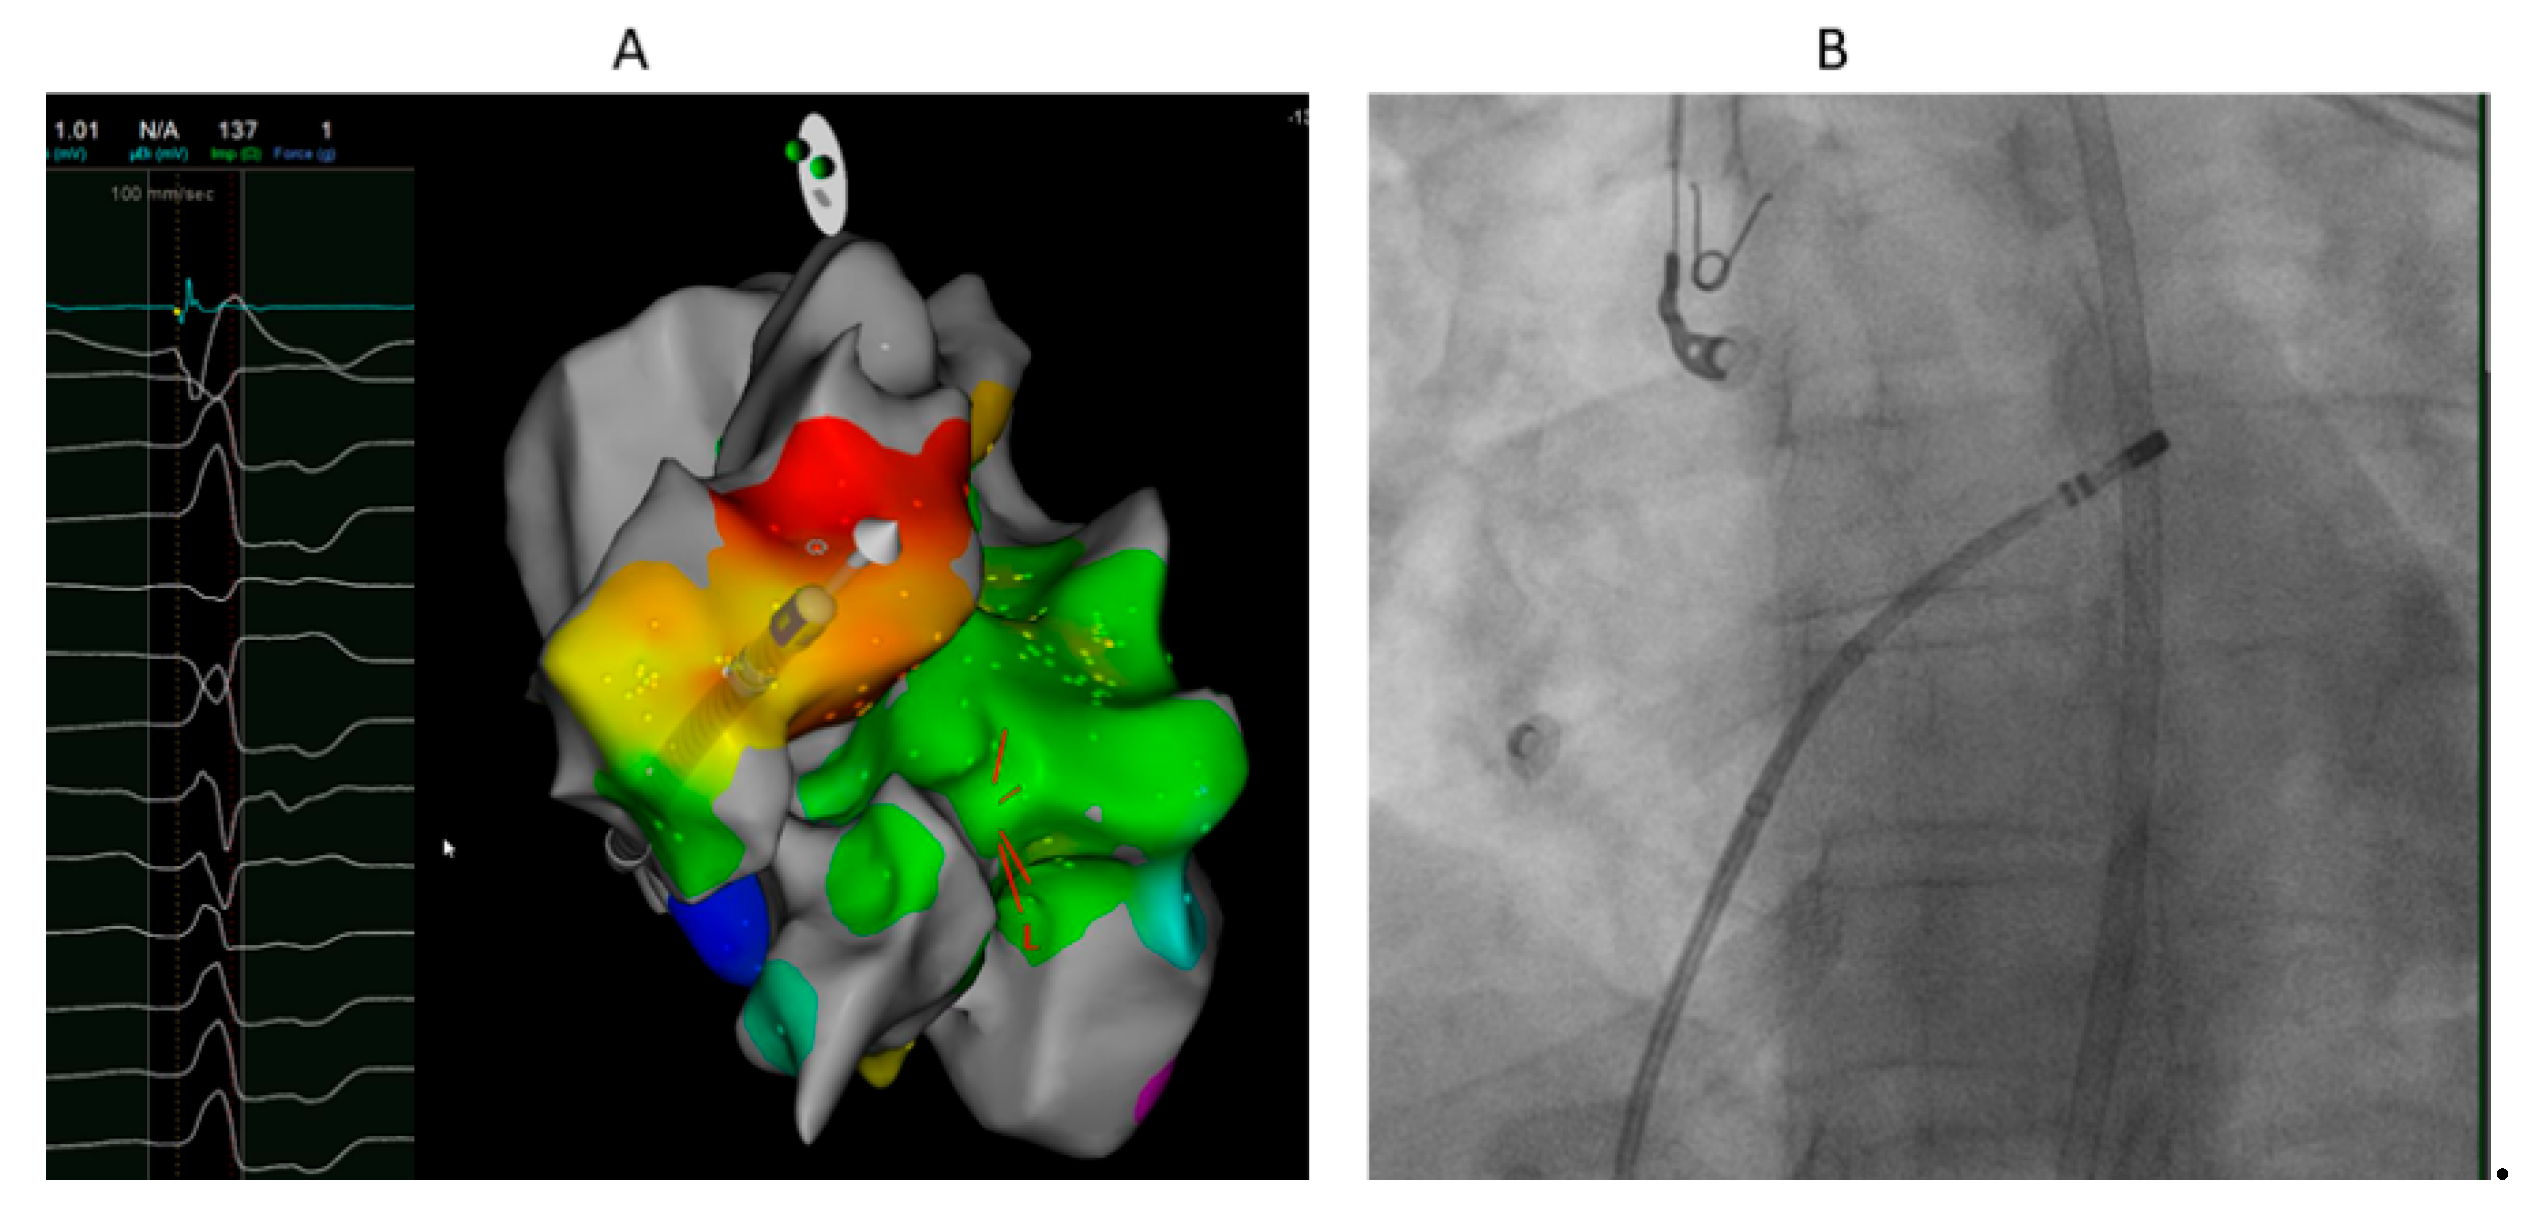

Ablation from GCV-AIV after failure of ablation from LVOT eliminated VA in 1 of 2 patients it was attempted. Ablation from RVOT only (at the anterior and leftward RVOT just under the pulmonary valve) was successful in 1 patient with R wave pattern break in V2 (Figure 3). Percutaneous epicardial ablation was attempted in 2 patients after failed endocardial ablation, but failed to eliminate the VA in one of them. Complications were not reported except pseudoaneurysm of the femoral artery treated by local thrombin injection.

Figure 3. 40 years old female with high burden VPCs with R wave pattern break in V2. A. Local electrogram at ablation catheter located at the anterior and leftward RVOT just under the pulmonary valve preceding QRS by 19 ms which was earlier than sites from LVOT and GCV-AIV. Ablation at this site eliminated the VPCs. B. LAO fluoroscopic projection showing the ablation catheter at the most anterior and leftward RVOT just under the pulmonary valve.